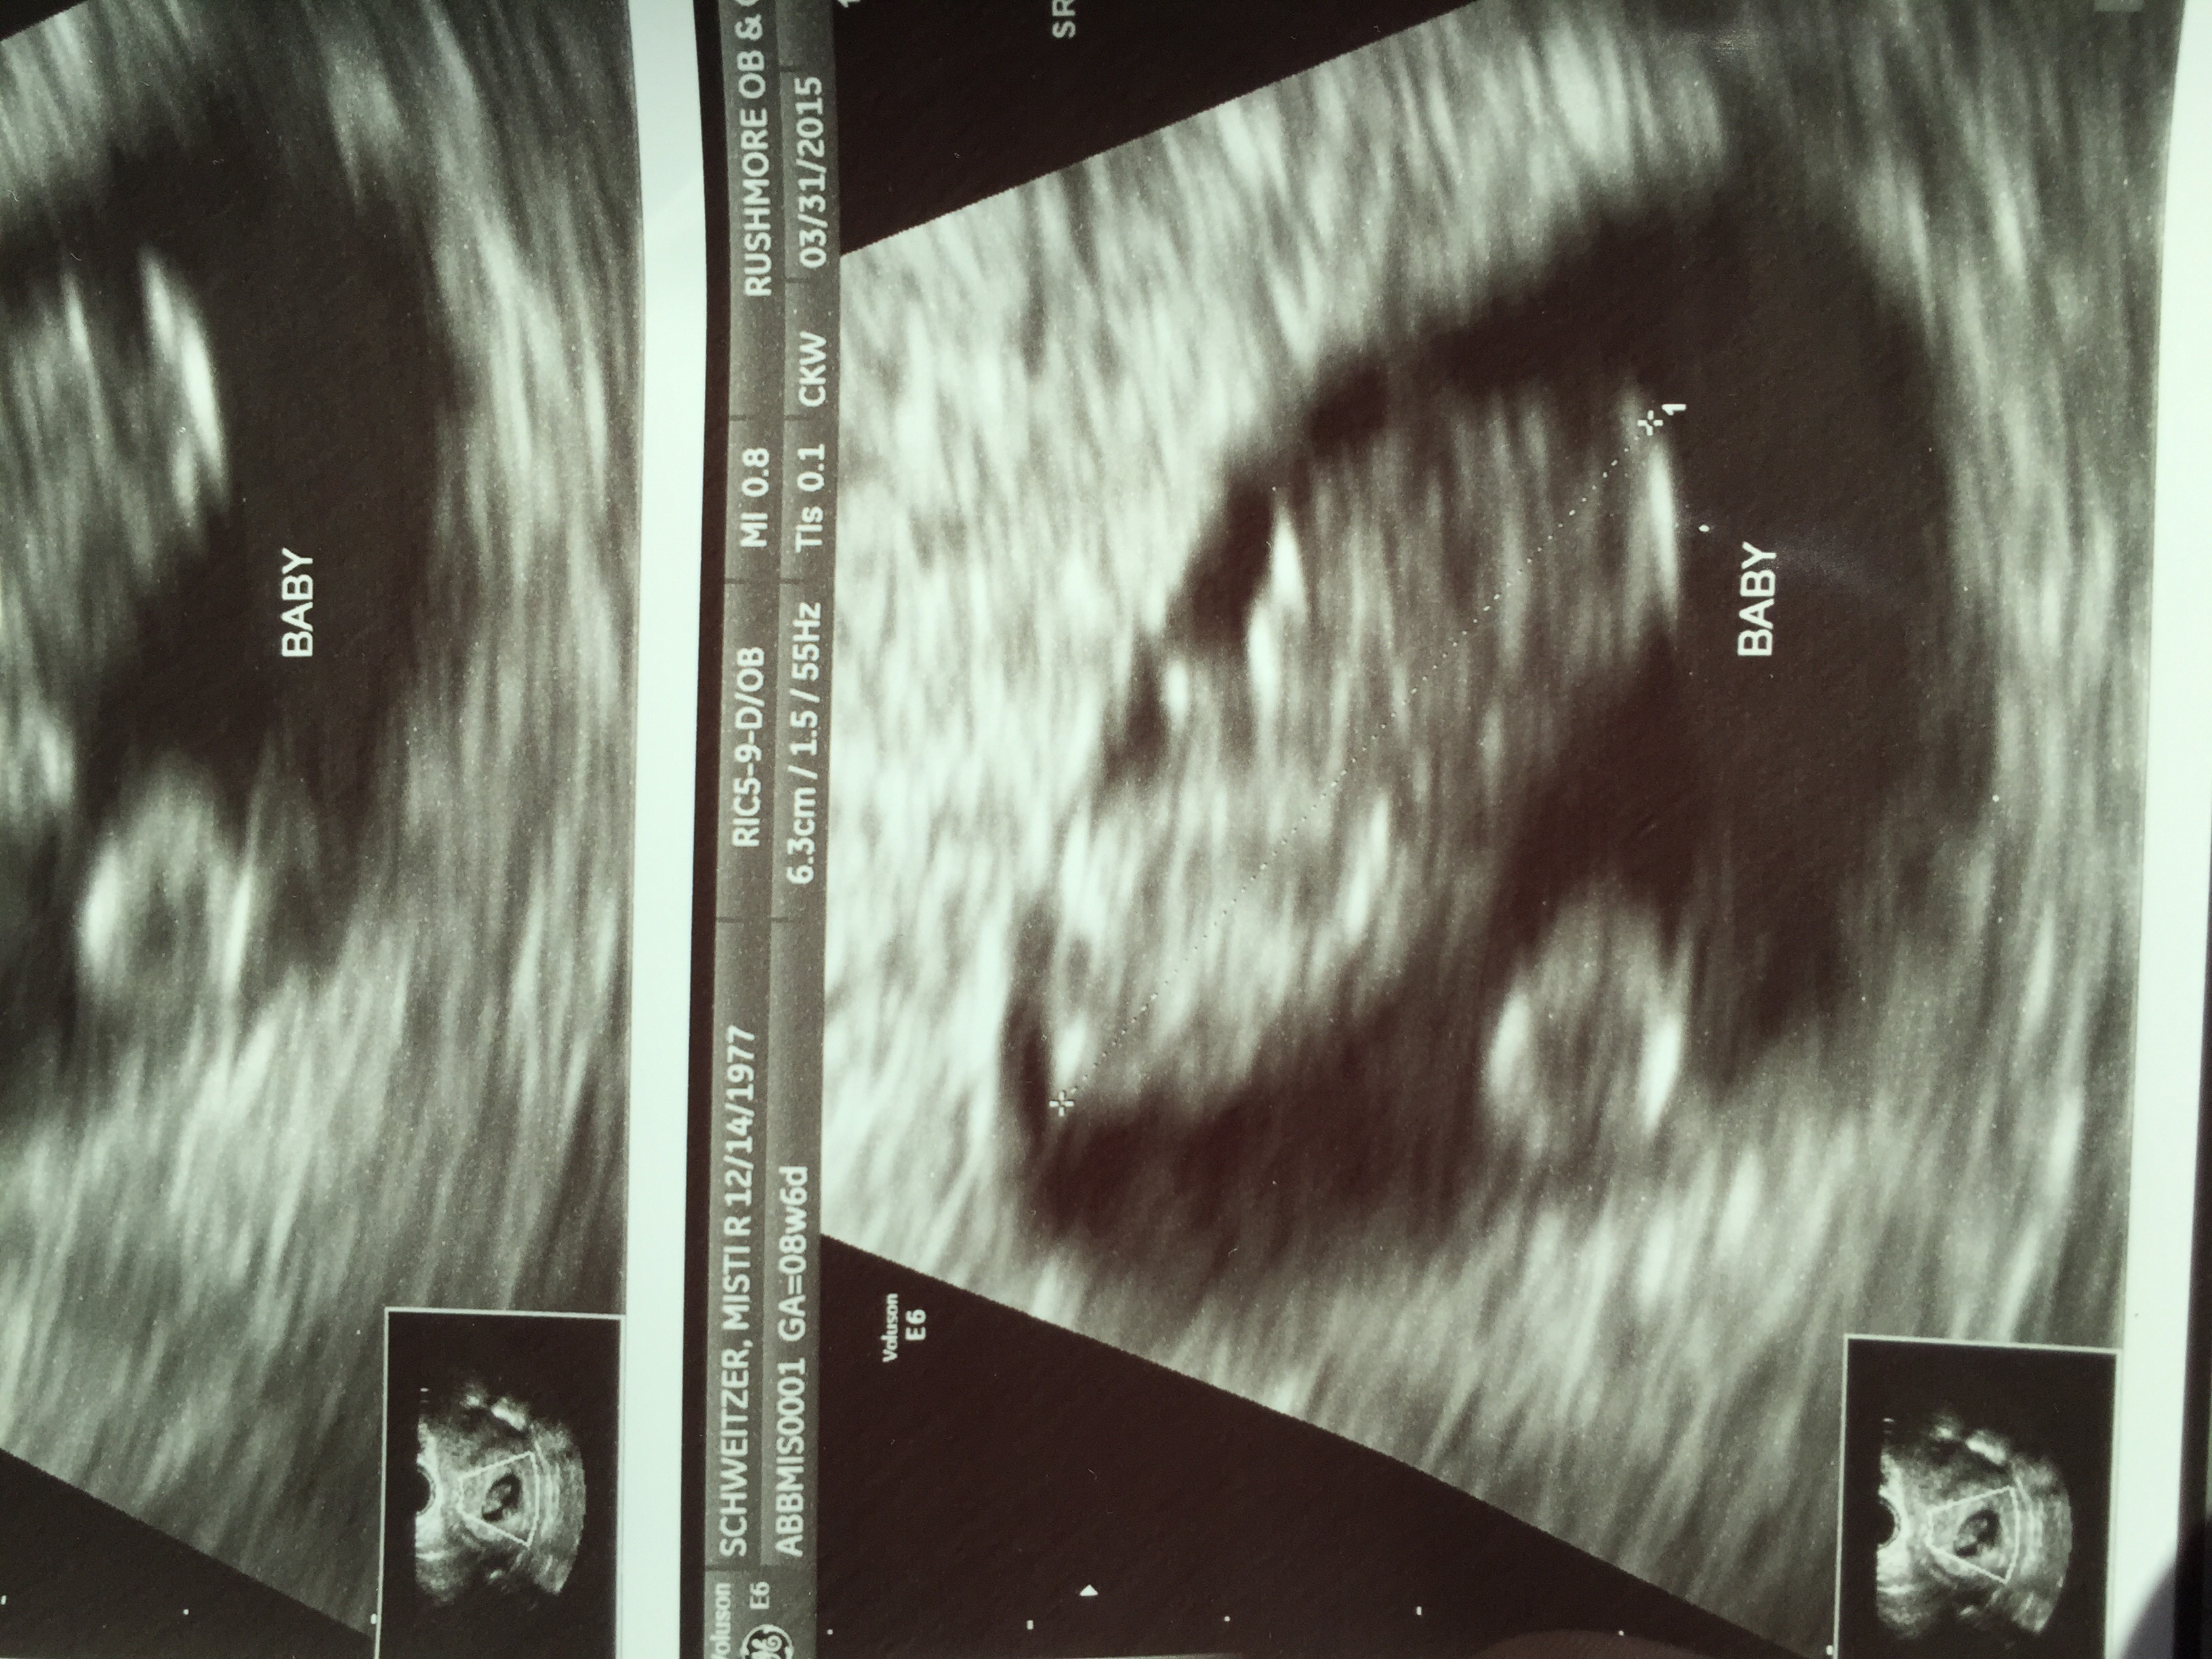

• Today at 8 weeks 4 days

• Our mini at 8 weeks 4 days :) heart rate was 177

8weeks and 1 day

Heartrate 165

Immediately in love !!